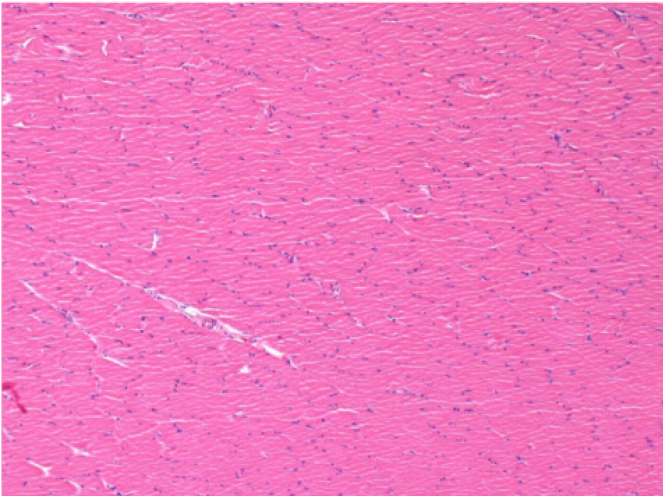

بعد 3 أشهر من حقن إندوبيل

3 أشهر (D90) بعد حقن Endopeel 0.1 مل في العضلة أمام الظنبوب اليمنى.

L : Control-100xD90

R:100xD90